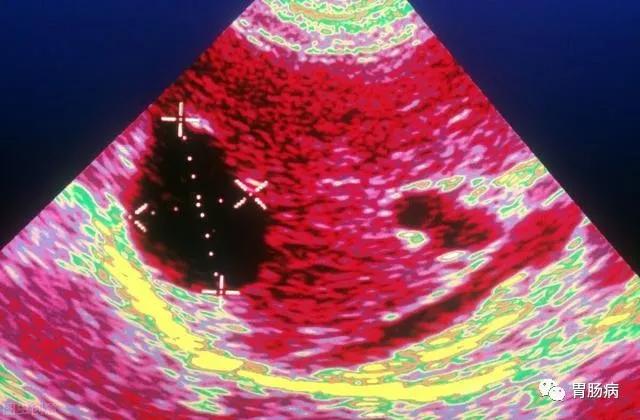

超声是最有效的初检手段,如果需要进一步鉴别,可以再做CT或者核磁共振,甚至穿刺针吸活检等检查。CT如下图所示

最常见的单纯性肝囊肿,在超声检查中表现为肝脏内部出现的澄清液体的囊性结构,偶然体检发现的无症状患者不需要对肝囊肿进行治疗,单纯性肝囊肿也不需要反复做检查。